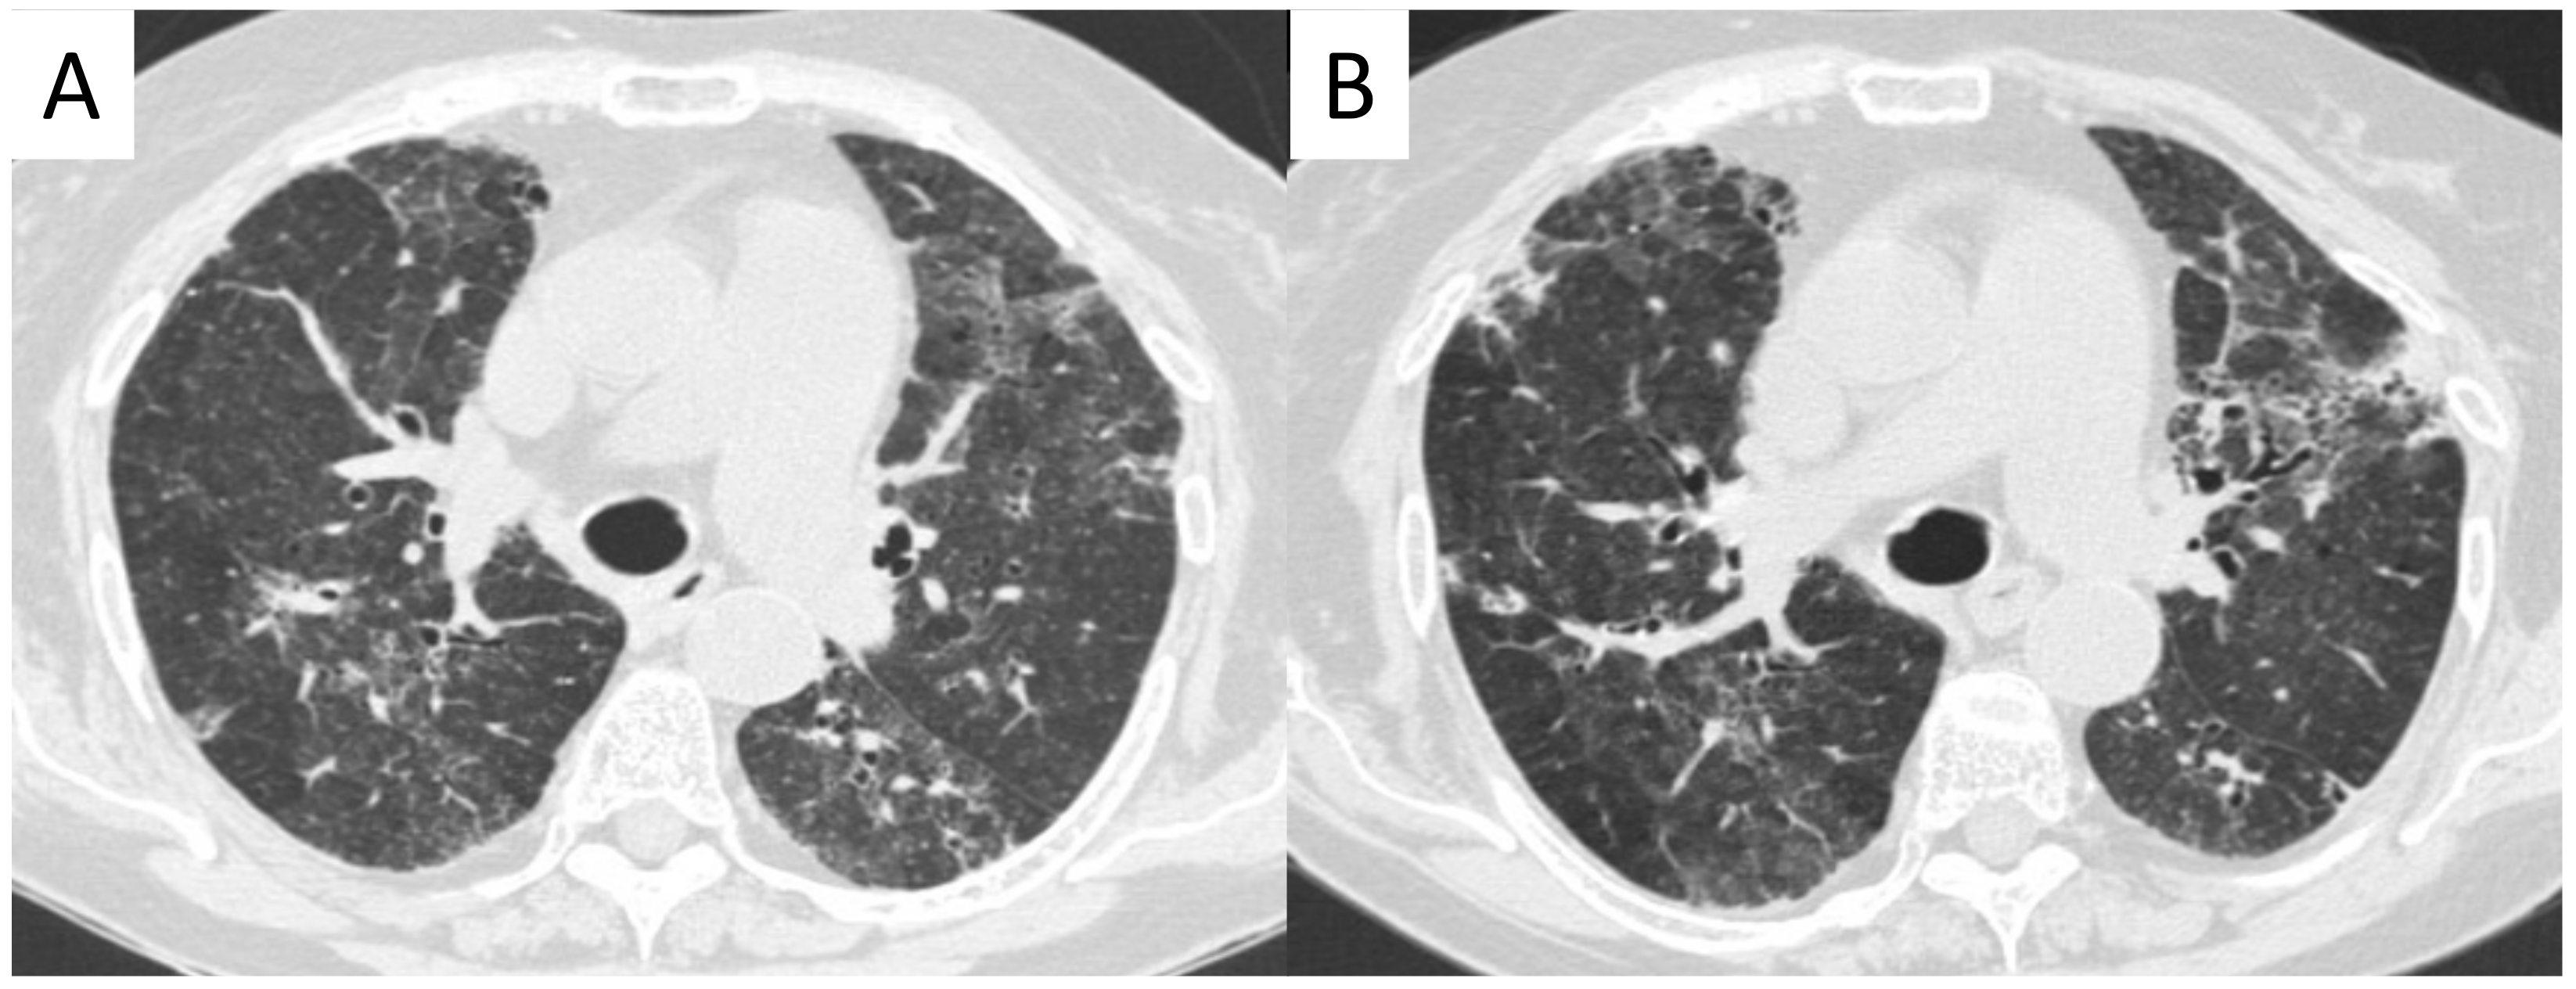

2.10.2. Morphological Patterns and Imaging

| Comarmond et al., 2014 | [26] | 49 ANCA and PF: Typical UIP 43% Atypical UIP 14% Fibrotic NSIP 7% NSIP 9,5% | Preceding 45% Concomitant 43% Posterior 12% |

| Foulon et al., 2008 | [27] | 17 ANCA and ILD: Probable PF 70% UIP 17% | Preceding 76% Concomitant 24% |

| Arulkumaran et al., 2011 | [28] | 194 MPA-14 MPA and ILD: Idiopathic pulmonary fibrosis: 57% DIP: 14% NSIP: 7% | Preceding 14% Concomitant 64% Posterior 21% |

| Tzelepis et al., 2010 | [29] | 33 MPA-13 MPA with PF: UIP 54% NSIP 31% | Preceding 53% |